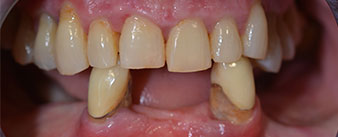

El tratamiento periodóntico necesario y la extracción de las piezas en el maxilar superior debía realizarse en un momento posterior, ya que la paciente es profesora y, en el momento de la consulta, estaba ocupada con los exámenes para las pruebas de acceso a la universidad. La paciente no podía comer ni hablar adecuadamente, ya que la prótesis temporal se rompía con mucha frecuencia y con una carga mínima.

Tras explicarle las distintas opciones de tratamiento, la paciente se decidió por la extracción de la dentición residual en el maxilar inferior, la implantación inmediata y el tratamiento con el método Fast & Fixed (bredent medical), con el que la prótesis dental fijada provisionalmente se atornilla sobre cuatro implantes en el mismo día de la intervención. El objetivo era operar a la paciente el viernes para que el lunes pudiera tomar parte en los exámenes orales para la prueba de acceso a la universidad.